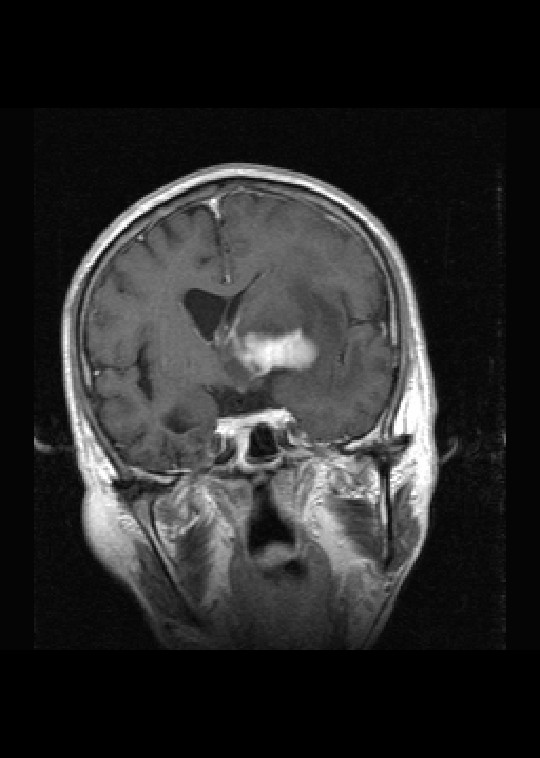

标题: MRI2527:脑部肿瘤,(病理结果:淋巴瘤)

(左额颞叶)非霍奇金淋巴瘤,b细胞性,弥漫性大b细胞型。免疫组化结果:cd45(lca) +,vimentin +,ck(ae1/ae3) -,ema -,cd3 -,cd20 +++,cd30 -,plap -,cd79a +,gfap -,alk -,s-100 -。

左侧基底节区病灶t1wi呈不均匀稍低信号,t2wi呈稍高信号,周围伴有水肿。增强扫描呈均匀团块样或者抱拳样明显强化,相邻的柔脑膜亦见线样强化。首先考虑淋巴瘤。可惜没有ct平扫,如果ct平扫病灶呈高密度,那么更支持pcnsl的诊断。

病理结果:(左额颞叶)非霍奇金淋巴瘤,b细胞性,弥漫性大b细胞型。免疫组化结果:cd45(lca) +,vimentin +,ck(ae1/ae3) -,ema -,cd3 -,cd20 +++,cd30 -,plap -,cd79a +,gfap -,alk -,s-100 -。

左侧基底节区病灶t1wi呈不均匀稍低信号,t2wi呈稍高信号,周围伴有水肿。增强扫描呈均匀团块样或者抱拳样明显强化,首先考虑淋巴瘤。